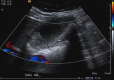

Gallbladder Carcinoma, the Difficulty of Early Detection: A Case Report

Gallbladder carcinoma (GBC) is an uncommon malignancy with a high mortality rate. Detecting gallbladder carcinoma in its early stages can be difficult, despite improvements in ultrasound and computed tomography (CT) imaging. Most diagnoses of GBC are made at advanced stages, with the majority being found incidentally during surgery for cholelithiasis. The presented case demonstrates the difficulty of diagnosing GBC preoperatively in its early stages.